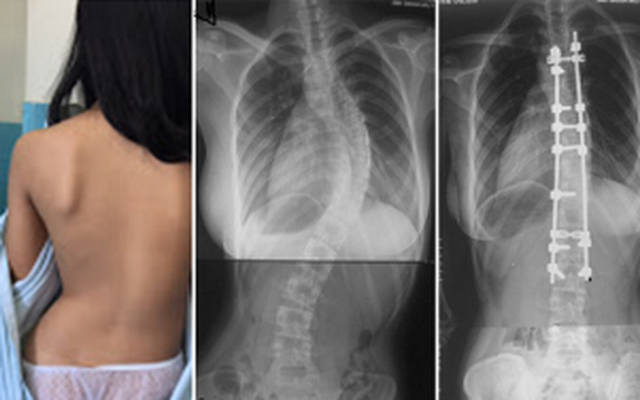

Các triệu chứng ngày càng rõ rệt khi bệnh tiến triển nặng hơn:

Sau đó các bác sĩ sẽ chỉ định đo chiều cao, cân nặng, tỉ số khối cơ thể (BMI), khám tổng quát tìm bệnh lý toàn thân, vùng cơ, xương, khớp, cột sống, biến dạng đường cong bình thường cột sống, gõ hoặc ấn vào các gai của đốt sống gây tình trạng đau hoặc khó thực hiện các động tác cúi, ngửa, nghiêng, quay thân mình.